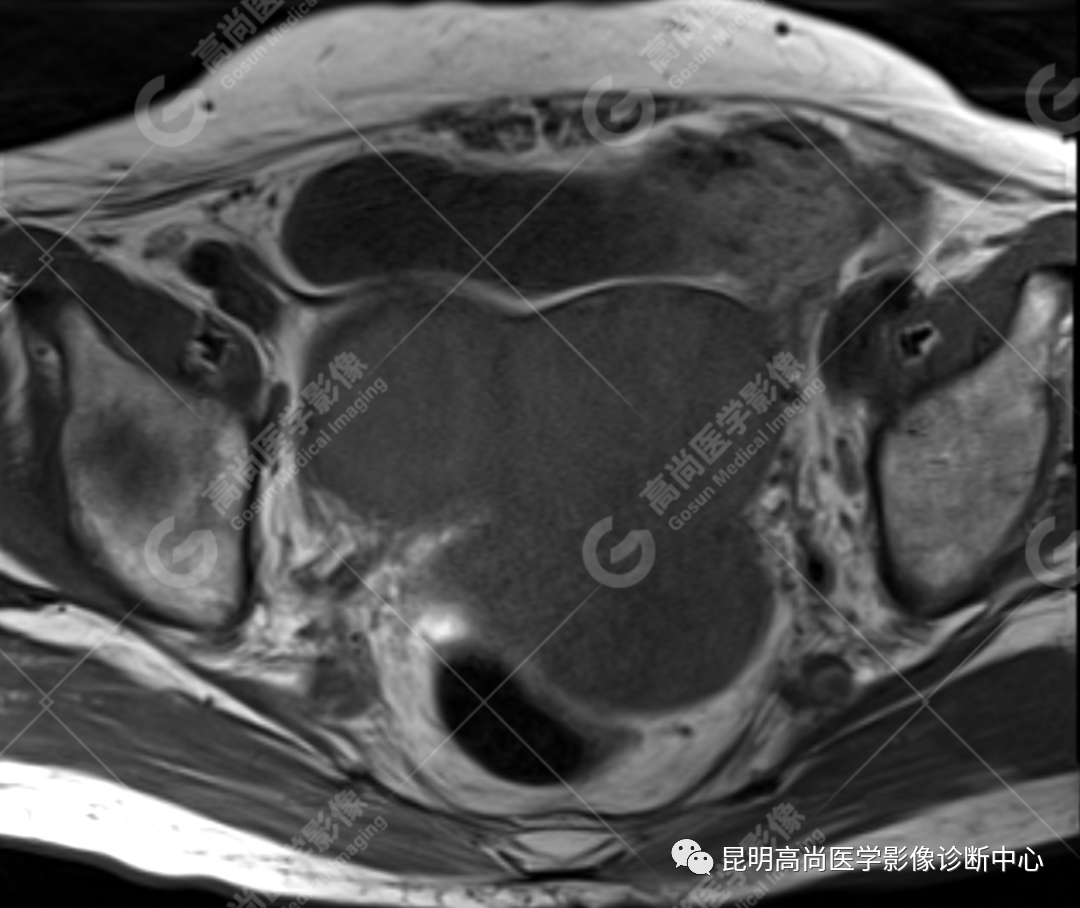

检查图像

影像诊断

子宫、附件未见显示;下腹部及盆腔内巨大占位,考虑恶性肿瘤,肉瘤可能,阴道及肛管受侵,建议活检。

MRI 表现

不规则菜花状或息肉状肿物,子宫内膜正常 T2WI 清晰连续的高信号消失,取而代之是中高、高信号,不均匀混杂信号,信号强度低于内膜正常信号强度,T1WI 上内膜信号增高,子宫肌层明显变薄,未受侵者肌层信号均匀,因肿物组织来源不同,病变信号复杂,以 T2WI 表现为等高混杂信号为主。因病灶较大,可合并囊变坏死及肿瘤出血。

小的子宫癌肉瘤显示为内膜肿块,不能与子宫内膜癌鉴别,大的肿块因坏死而与子宫平滑肌肉瘤相似。